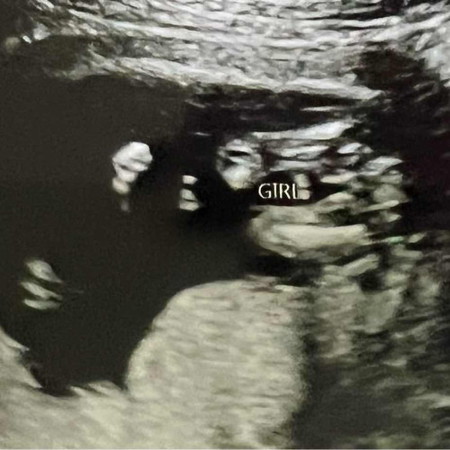

15w2d หมอบอกว่ามีแนวโน้มว่าเป็นผู้หญิง (เห็นกลีบ) แม่ๆดูออกกันมั้ยค่ะ ว่า ญ หรือ ช